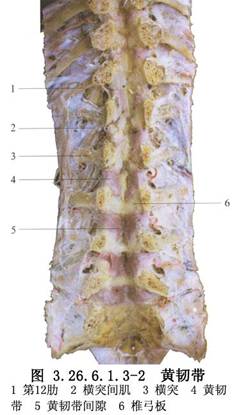

脊柱節段性器械是1973年Luque首先創用的,其特點是在脊柱矯形區內的多個椎體節段上,用鋼絲通過椎板下或棘突基底部將矯形棒固定於椎體上進行脊柱矯形。Luque棒和記憶合金棒均屬於脊柱節段性器械。手術相關解剖見下圖(圖3.26.6.1.3-1~3.26.6.1.3-3)。

沿棘上韌帶切開,顯露至棘突,先行脊柱凹側面分離。使用Cobb剝離器以棘突爲支點,緊貼棘突及椎板骨面向外側推開椎旁組織直到關節突,邊剝離邊用紗布填塞止血,依次行相鄰椎板分離顯露。胸椎向兩側顯露至橫突尖,凸凹側均行廣泛鬆解,切除橫突間韌帶及肌肉,胸腰椎均行關節切開術。

9.3 3.黃韌帶開窗

(1)腰椎部分:將棘間韌帶切除,用布巾鉗將上下椎骨的棘突提起,幫助顯露椎板間隙,咬骨鉗稍咬除棘突根部的椎板骨質,擴大骨孔即可看到兩側黃韌帶及其中央縫隙。用銳頭的尖嘴咬骨鉗一小塊一小塊地咬除黃韌帶,直到硬膜外脂肪顯露出。

用剝離子探入黃韌帶下輕輕推離,以分離硬膜與黃韌帶粘連,此時換用小椎板咬鉗小心探入黃韌帶深面擴大咬除黃韌帶,至椎板間骨孔擴大到5~8mm直徑爲止。整個操作過程應注意勿損傷硬膜,用棉片輕輕填塞骨孔,減少周圍血液流入硬膜外腔。

(2)胸椎部分:除切除胸椎棘間韌帶外,尚需將覆蓋在椎板間隙上的棘突咬除,才能進行黃韌帶開窗術。由於胸椎椎間隙較狹窄,常需咬除部分椎板以擴大骨孔。在主彎頂部附近的幾節椎板間隙,可將凸側椎板楔形切除到關節突,以利脊柱矯形(圖3.26.6.1.3-9,3.26.6.1.3-10)。